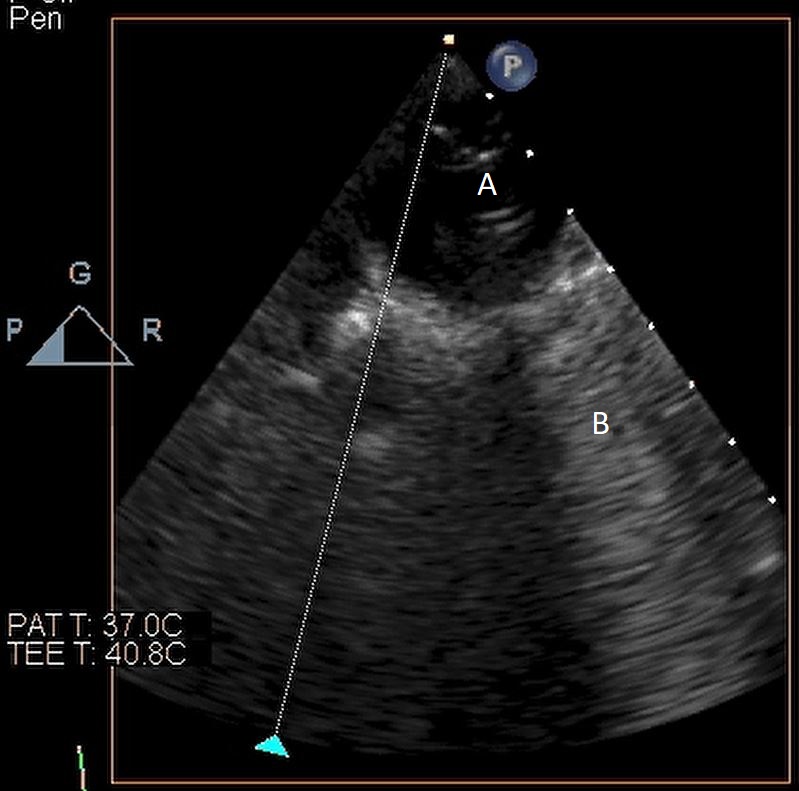

When examining the inflow cannula of the LVAD, the inflow cannula should be orientated and aligned with the mitral valve [47] (Figs. 19,20). Laminar flow from the ventricle to the device suggests a correctly aligned inflow cannula [56]. Obstruction of the inflow cannula manifests with increased turbulence and elevated doppler velocities [47].

Fig. 20.Transesophageal echocardiogram four chamber image with the LVAD inflow cannula pointing towards the septum (A). (B) LV (C) LA.